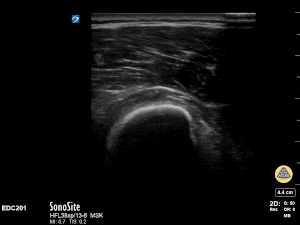

12y male presenting with RUE pain after bike injury. POCUS demonstrating proximal humeral fracture. Long axis and short axis views of fracture. Matthew Moake, MD PhD